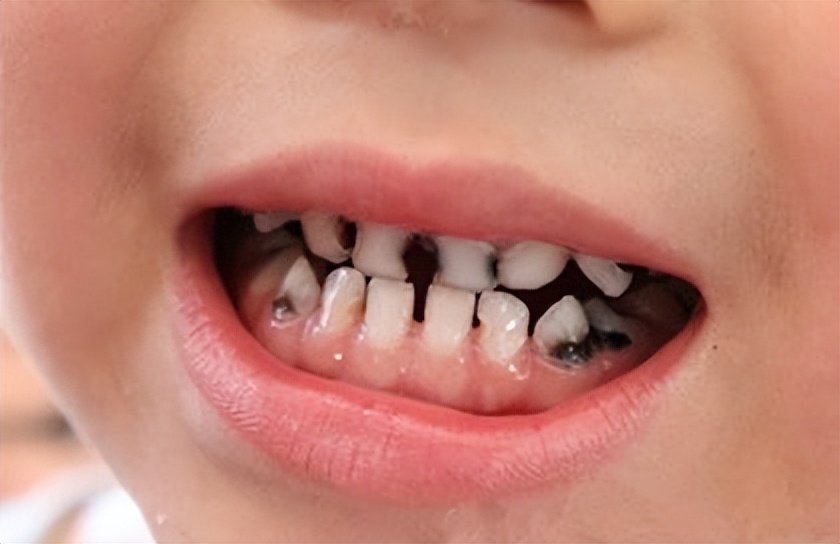

比如这样的:

这样的: